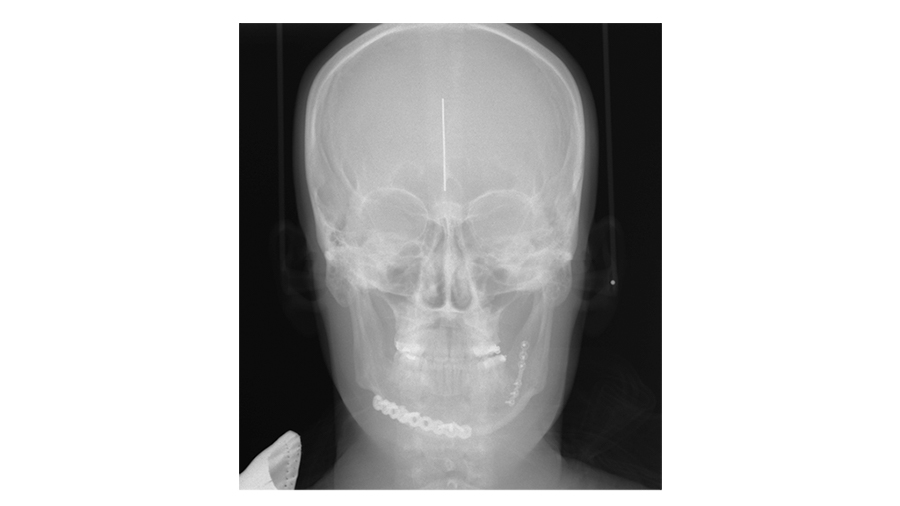

So, you have your Panorex - what are you looking for on your PA film here?

Dr. Susarla: The PA film—what I'm looking for is just the splay at the inferior border. One of the advantages of the Panorex is that it's sort of the workhorse for dentoalveolar imaging, particularly for the mandible. It shows you the condyles, it shows you the inferior border, it shows you the teeth, and it can show you the positioning of the fixation relative to the roots of the teeth.

One of the downsides of the Panorex is that it doesn't show you the transverse dimensions. If there's a little bit of lingual splaying, you might not be able to see that as well. My protocol is, particularly in young patients, if there's no compelling reason to get a postoperative CT scan, then I just get plain film imaging to verify to myself that the reduction is adequate and that the hardware looks okay.

And I'd like to get two planes of imaging, so a Panorex, and in this case, a PA ceph[alogram] to be able to show the entirety of what you would imagine three dimensionally or the information you get from a 3D CT scan just with a lower radiation dose.